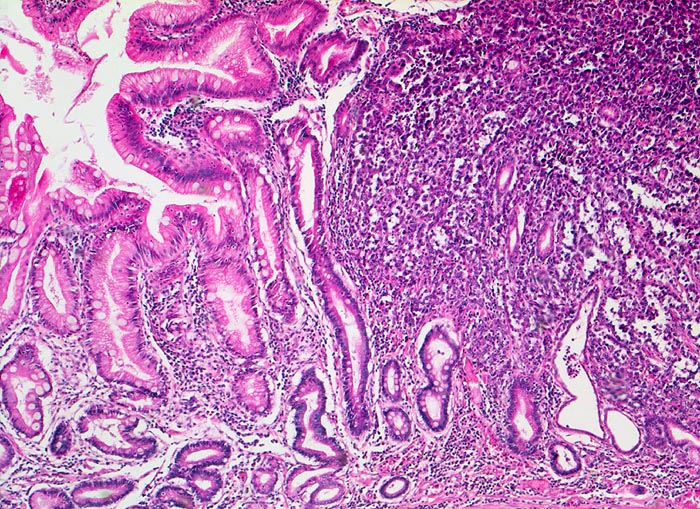

PathoPic – image database / PathoPic ID 5063 - Magenfrühkarzinom

Magenfrühkarzinom

Magenantrum

Links im Bild die Magenschleimhaut mit intestinaler Metaplasie (zahlreiche Becherzellen). Diffuse Tumorinfiltration mit Verdrängung und Umwachsung der ortsständigen Magendrüsen rechts im Bild. Der abgebildete Karzinomanteil ist gering differenziert. Die hochgradig atypischen Tumorzellen bilden nur andeutungsweise erkennbare Drüsenschläuche.

Endoskopische Kontrolle bei Patient mit bekannter chronischer Gastritis.